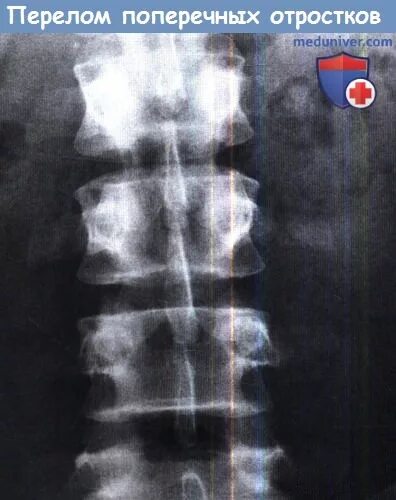

Перелом отростка l2